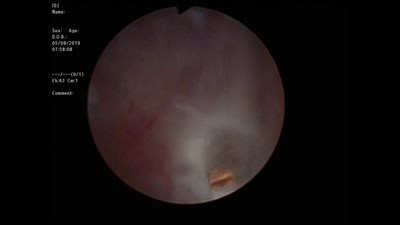

Чрескожная нефролитотрипсия

Оперирует Сорокин Николай Иванович.